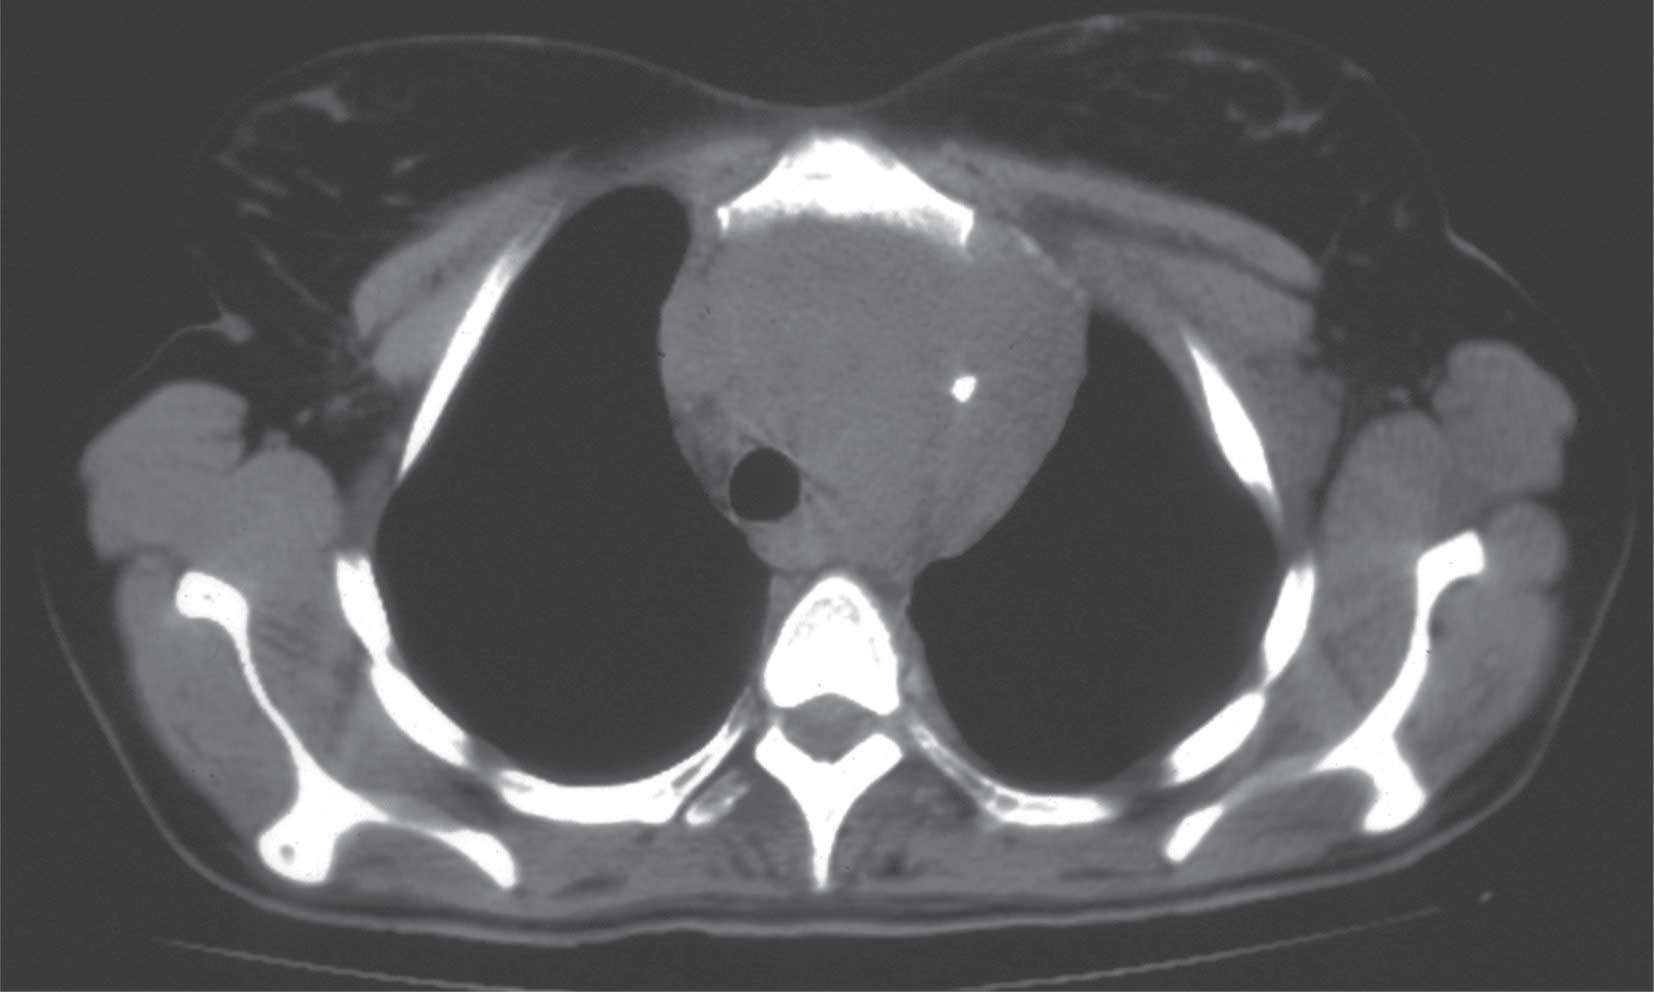

و- السطام التأموري:pericardial tamponade ينجم السطام التأموري الحاد عن نزف حاد ضمن التأمور، وتنجم خطورته عن ضغط أجواف القلب ولاسيما الوريدية منها، مسببة صدمة قلبية cardiogenic shock.

يتظاهر بالزلة التنفسية والزرقة والصدمة وانتباج أوعية العنق وخفوت أصوات القلب وبالضغط التفاضلي العجائبي (هبوط الضغط الانقباضي 10ملم زئبق في أثناء الشهيق) وتكون الأصوات التنفسية طبيعية في الجهتين.

يتأكد التشخيص بارتفاع الضغط الوريدي المركزي CVP فوق 15ملم، وظهور الانصباب بفحص القلب بالصدى ضاغطاً الأجواف القلبية. ويتضمن التدبير الإسعافي بزل التأمور، والتدبير النهائي فتح الصدر وخياطة جرح القلب.